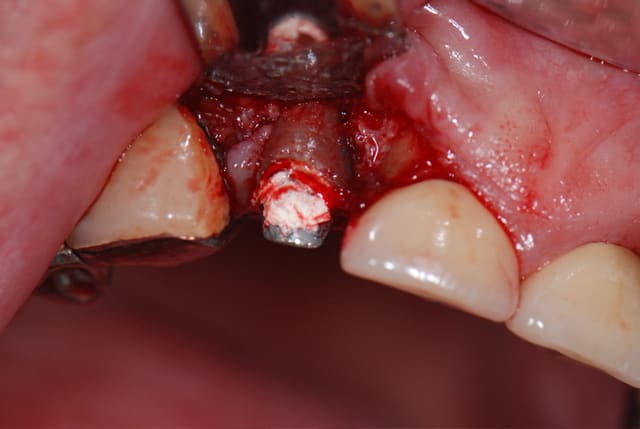

après forage du puit en ø 3, j'ai testé le site et j'ai compris tout de suite que ça n'allait sans doute pas se passer comme d'habitude, le foret bougeait trop à 15 mm; j'ai quand même continué en ø 4 et mis le taraud pour voir; ça a bien bloqué mais j'étais sceptique; le problème, c'est que ça saignait aussi de façon anormale; j'ai donc décidé de soulever le lambeau en PE pour voir ce qui se passait....je n'ai pas été déçu; j'ai cureté le TG qui était externe à l'alvéole, j'aurais d'ailleurs pû y penser tout de suite en voyant la racine, et j'ai changé d'objectif : plus d'implant mais comblement seul; j'ai refermé avec le TCP et la membrane de collagène que j'ai quasiment intégralement recouverte par un lambeau d'épaisseur partielle; la membrane devrait s'exposer un peu mais ça se gère habituellement sans problème

on voit sur la photo la technique d'ouhayoun (et consorts?) pour découper la membrane avec le carton d'emballage stérile de la suture, suture d'ailleurs dite "de la peau des f...." de chez ethicon en vicril + à 350€ les 36 pièces de 45 cm; c'est mon premier essai avec, on verra ce que ça donne; la membrane est en collagène résorbable, ça marche très bien, j'en utilise depuis 15 ans; voilà, il fait un grand ciel bleu dehors, ça me consolera (il ne pleut pas toujours en bretagne;-) )